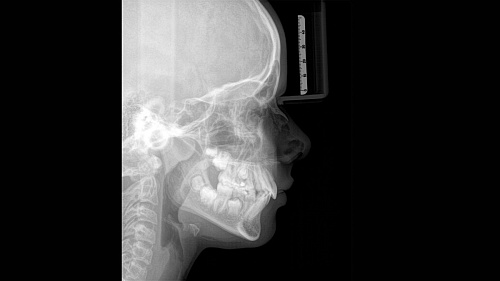

При помощи такого оборудования специалист сможет успешно решить широкий спектр диагностических и лечебных задач. Качественное изображение, достоверность при разноуровневой резкости (технология Sharp Layer), гибкий объём, 30 доступных вариантов цвета. Цефалометрическая визуализация позволяет получать боковые или симметричные снимки, а также определить положение при смещении зуба. Работая при разрешении до 80 мкм в режиме низкой дозы и HD, вы получаете качественные изображения выбранного формата, заботясь о комфорте и безопасности пациента.

Диагностика последнего поколения, идеально решающая задачи рентгеновского обследования независимо от размеров клиники. Поля изображения зависят от определенной клинической картины, поэтому специалистам так удобно работать с ORTHOPHOS SL 3D. Данная установка делает объёмные картинки для одиночной реставрации в 3D качестве полностью всей челюсти такого размера, которого требуется.

Датчик DCS служит для выставления резкости снимков, причём его технологические особенности можно считать революционными для современного рынка стоматологического оборудования.

Планирование одиночной реставрации, эндодонтические исследования и пр. – для этого специалист может выбрать объёмные варианты 8 х 8 см или 11 х 10 см, также предлагается объём 5 х 5,5 см. Снимки в HD-качестве, стандартные настройки или выбор объёма обследования в зависимости от диагноза — всё это врач получает в отличном качестве, а для пациента излучение в районе исследования минимально.

Конструктивные особенности датчика DCS заключаются в превращении рентгеновского излучения в электрическую энергию. Обычная для таких случаев промежуточная стадия светового луча отсутствует. Другими словами, значительно снизив потери сигнала, производитель максимально улучшил чёткость.

С технологией SL можно за один сеанс получить огромное количество снимков. Те из них, где фокусировка наиболее чёткая, автоматически соединяются. В итоге одна процедура — снимки челюсти полностью в самом лучшем качестве. Даже нестандартные случаи не станут помехой в обследовании. К примеру, при ретинированных зубах уже после того, как снимок сделан, нужную область можно выделить подробнее, и в ещё одном рентгене необходимость отпадает.